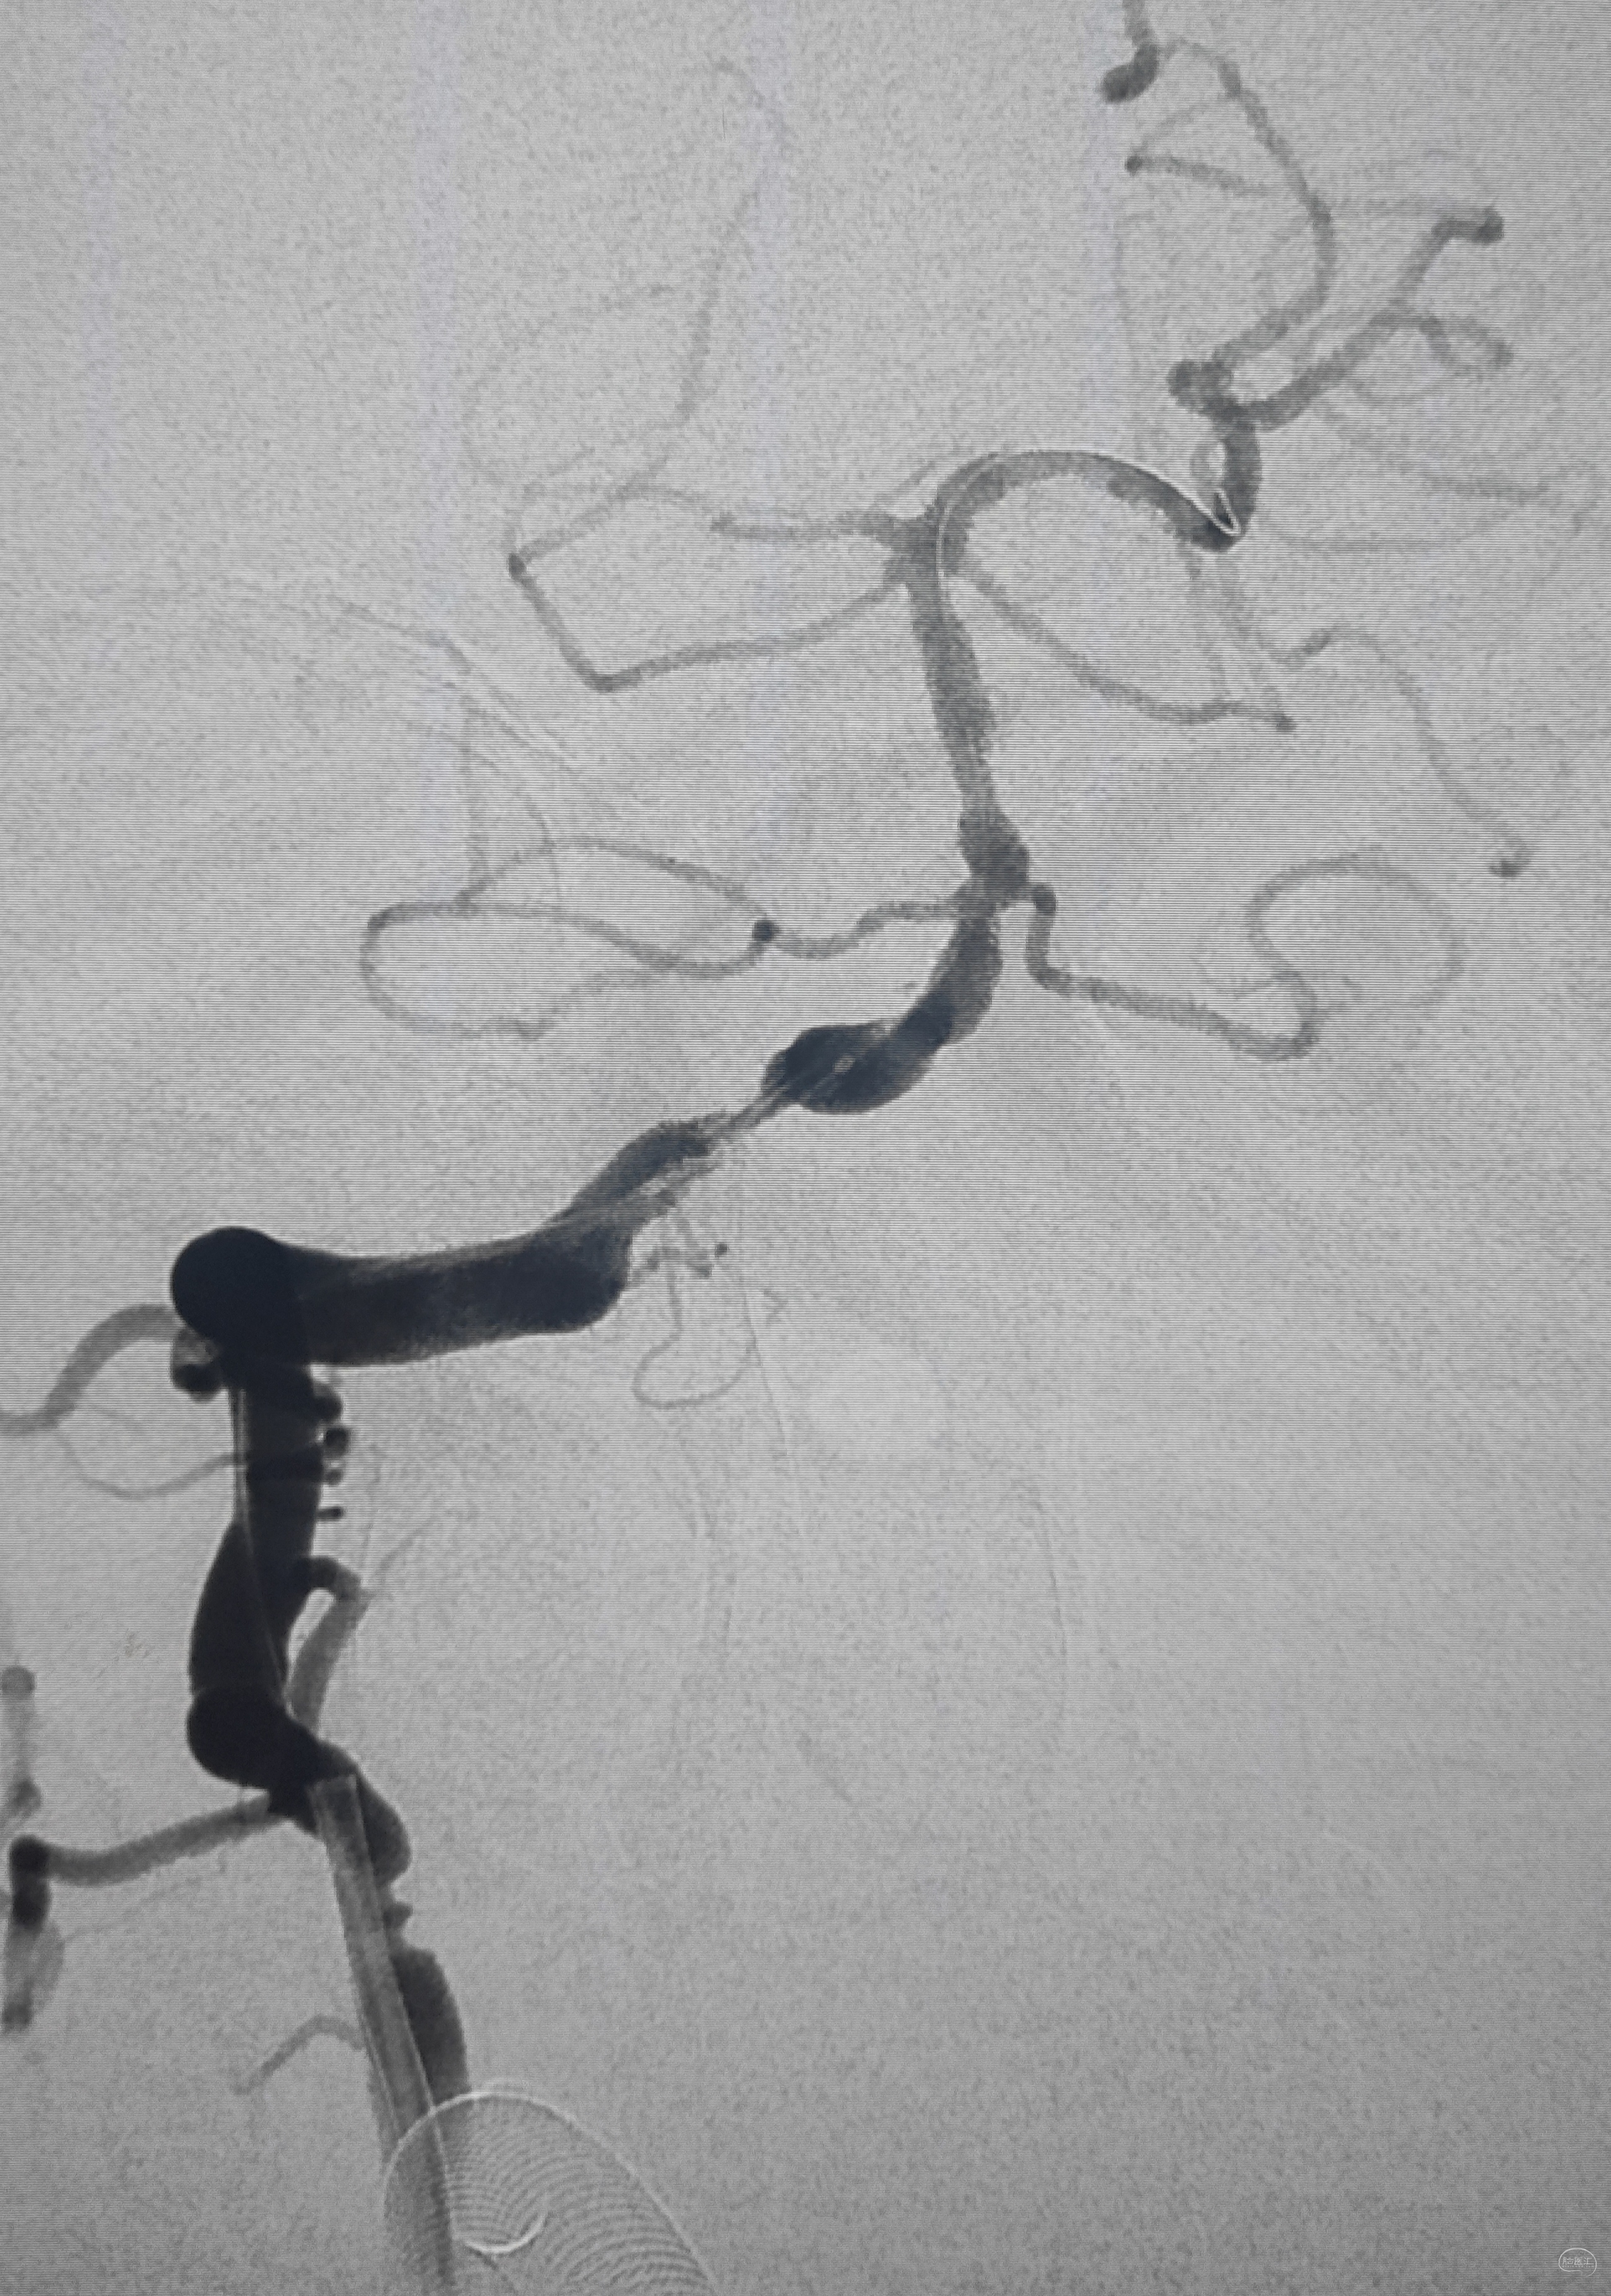

弓上造影初见:问题(一)左侧锁骨下动脉闭塞,主诉为头晕,双上肢收缩压差>20mmHg,这就是祸根?接着看弓上造影晚期像。

弓上造影晚期:剂量因素,逆流盗血隐隐可见,复合预期,那就看看对侧椎动脉情况吧

右侧锁骨下造影:右侧椎动脉开口也是重度狭窄,血流速度缓慢,闸门效应明显,此刻,不禁感叹血管的伟大,自己都狭窄得不要不要的了,还努力给对侧代偿供血,奉献精神佳!

右侧颈总动脉正侧位造影:意料之外的是,枕动脉通过肌支与右侧椎动脉吻合(紫色箭头),像极了《大风吹》的歌词“借一杯天上的水”,源源不断进行着血流的补充。但是好景不长,同侧V4段明显狭窄,无情的设置了第二道坎(绿色箭头)。